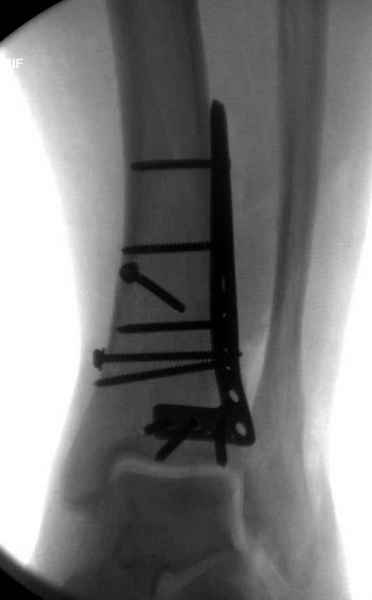

В данном случае ориентир сохранен, малоберцовая хорошо сочленена с тараном. Но несмотря на отсутствия перелома на снимке, все-таки для страховки можно было бы сделать снимок проксимальной части конечности.

Любая фиксация - преконтурированные пластины с уголовой стабильностью, медиальная, латеральная в зависимости от нахождения отломков или наружная фиксация типа аппарата Илизарова подходят для ранней мобилизации.

Не все переломы пилона фиксируются медиальной

пластиной, поэтому, учитывая что большой фрагмент

находится на латеральной стороне, я бы применил

передне-латеральную пластину.